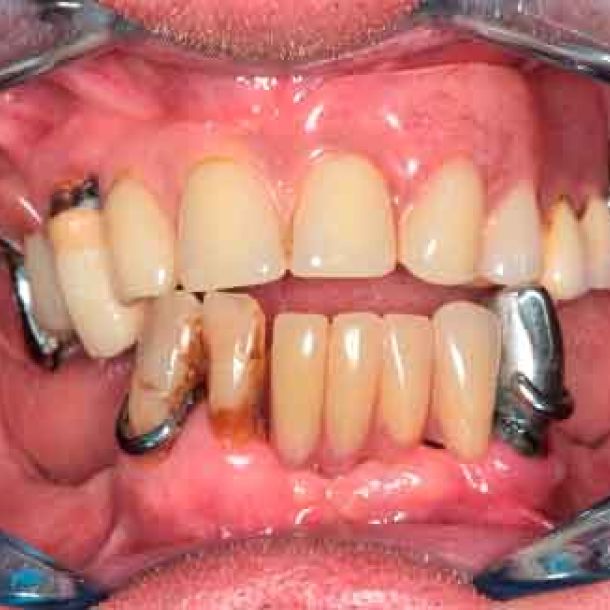

66 years old patient. Wishes to regain functional comfort and improve aesthetics.

Complaints :

- Lack of stability of his removable prosthetics

- Difficulties in eating

- Sagging of the upper lip

The periodontal structures of the remaining teeth are no longer sufficient. An edentulism is considered. The treatment plan is directed towards a removable maxillary complete prosthesis and an implant-supported mandibular complete prosthesis.

Picture - Initial bite situation